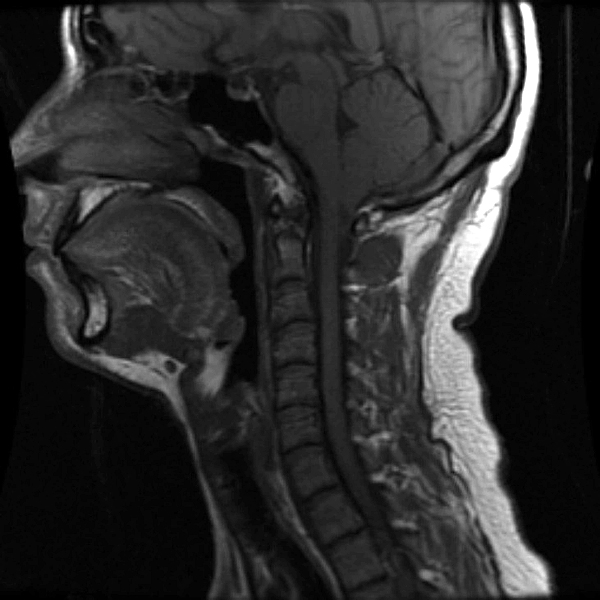

once i got back home and checked out my scans in osirix (the mac os x application to view DICOM medical imaging slides), i was blown away. talk about invasive: you haven't seen intimate until you've looked at photos of the inside of your body. the coolest part is since the scans were done in cross-sections, i can animate the scans so it looks like the beam is passing through my neck and head (all 800+ images). i've always known that inside my body was all sorts of muscles and veins and organs, but i guess i was hoping for something less messy, maybe circuit boards and memory chips instead. i know MRI's were first used in the late 60's, but this is my first time experiencing the technology in-person and it's pretty amazing. talk about futuristic! to be able to see with so much detail the insides of my body without having to cut me open! if scientists can do this, what else can they do? my only regret is they only imaged me from my shoulder up. i'd love to have a full-body scan. maybe i can fake some sort of internal injury and get my doctor to okay the procedure. i recommend anyone who's never had an MRI done to do so when they have the chance.

speaking of doctors, the main reason why i was at MGH this morning was for a follow-up appointment with my doctor. he basically told me that my MRI scans were fine as well as my blood work (he wrote me a letter a few weeks ago, so i already knew the news). since the pain in my neck had already disappeared,

i wasn't disappointment that we never figured out what was the cause. however, i did want to talk to him about the muffled hearing i've been experiencing in my left ear since as far back as october. he checked my ear and it seemed normal: no inflammation, no perforated eardrum. a look down my throat revealed nothing as well. lacking anymore clues he decided to throw a bunch of drugs at me to see if it'd clear up my sinuses, which seemed to be the root of the problem. besides taking some claritin-D (pseudoephedrine sulfate & loratadine), he also told me to take some sudafed as well (pseudoephedrine hydrochloride), a combination of antihistamine and decongestant. that's followed my some afrin nasal spray (oxymetazoline hydrochloride) plus the prescription strength nasal spray flonase (fluticasone propionate).